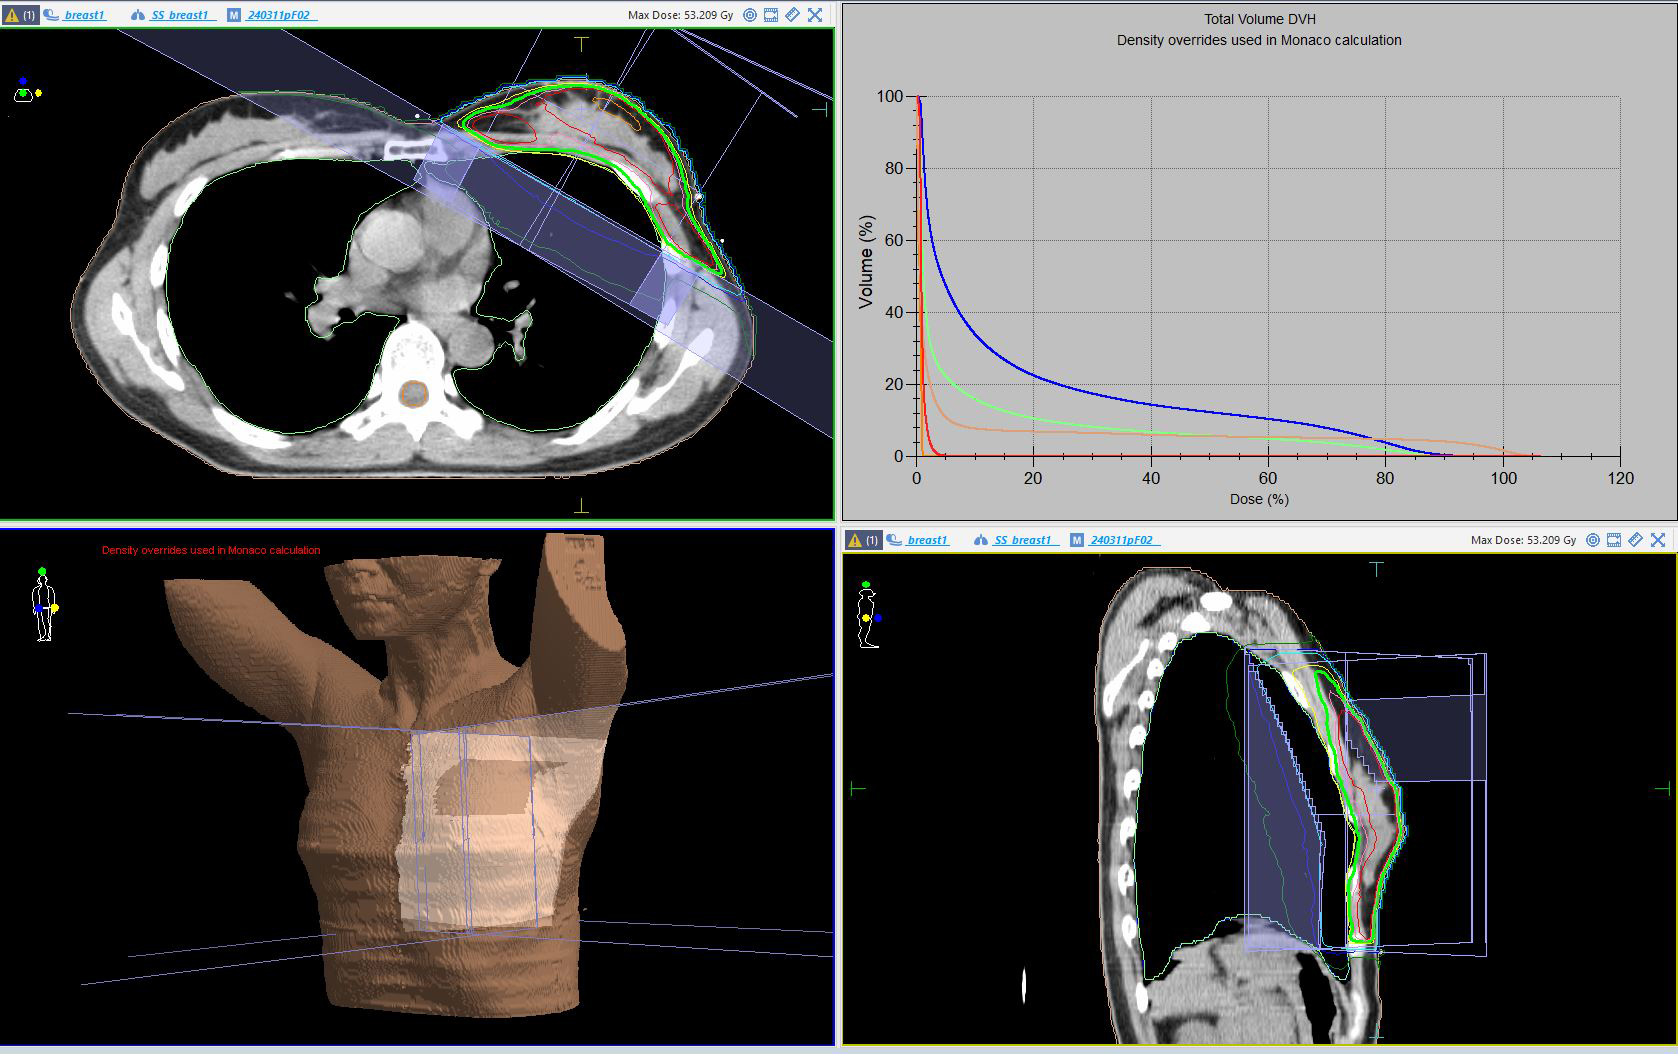

3.放射線治療計画の作成

治療計画用CTで得られた画像をもとに、放射線治療医が放射線治療計画装置を用いて、照射範囲・放射線量・照射回数を決定します。

がん細胞に十分な線量を照射すると同時に、周囲の正常な組織への影響をできるだけ抑えるよう、慎重に治療計画を立てます。

当院の放射線治療計画装置(Monaco)で作成した乳房接線照射の一例